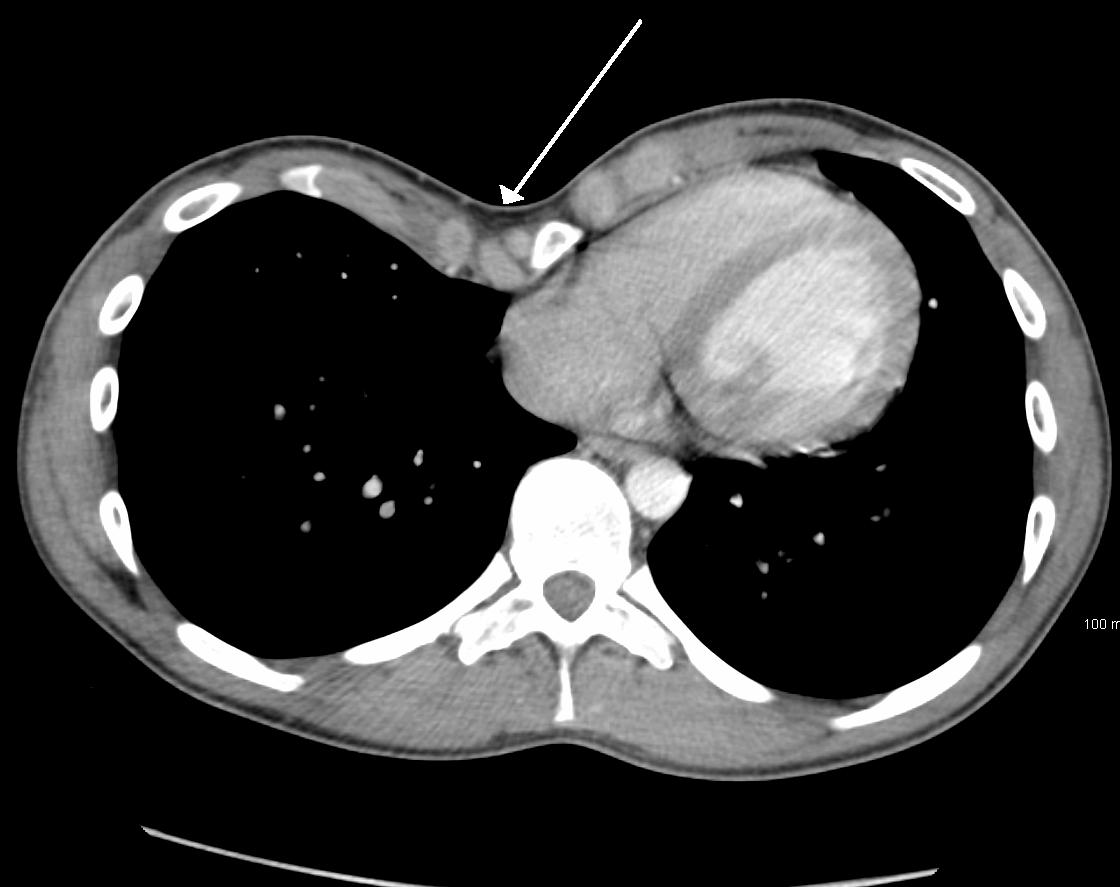

가슴 벽 변형 정도를 결정하기 위해 여러 척도가 개발되었다. 이들 대부분은 흉골과 척추 사이의 거리를 변형한 것이다. 그중 하나는 칼돌기에 가장 가까운 척추체의 직경과 칼돌기와 가장 가까운 척추체 사이 거리의 비율을 기준으로 변형의 심각도를 평가하는 ''Backer ratio''이다.[15] 최근에는 CT 스캔 측정에 기반한 Haller 지수가 사용된다. 3.25 이상의 지수는 종종 심각한 것으로 정의된다.[16] Haller 지수는 늑골 안쪽의 수평 거리와 척추와 흉골 사이의 최단 거리 비율이다.[17]

오목가슴은 우선 앞가슴을 육안으로 검사하여 진단한다. 가슴을 청진하면 심장 박동의 위치 변화와 판막 탈출증을 확인할 수 있다. 흉골과 폐동맥이 가까워 수축기 동안 심잡음이 들릴 수 있다.[14] 폐 소리는 보통 깨끗하게 들리지만, 폐활량이 줄어들어 약해질 수 있다.[64]가슴 벽 변형 정도를 파악하기 위해 여러 척도가 개발되었다. 대부분 흉골과 척추 사이 거리를 변형한 것이다. 그 중 하나는 ''Backer ratio''인데, 칼돌기에 가장 가까운 척추체의 직경과 칼돌기에서 가장 가까운 척추체 사이 거리의 비율을 통해 변형의 심각도를 평가한다.[15] 최근에는 CT 스캔을 기반으로 한 Haller 지수가 사용된다. 3.25 이상이면 심각한 수준으로 본다.[16] Haller 지수는 늑골 안쪽의 수평 거리와 척추와 흉골 사이의 가장 짧은 거리의 비율이다.[17]

가슴 벽 변형 정도를 결정하기 위해 여러 척도가 개발되었다. 대부분 흉골과 척추 사이의 거리를 변형한 것이다. 이 중 하나는 칼돌기에 가장 가까운 척추체의 직경과 칼돌기와 가장 가까운 척추체 사이 거리의 비율을 기준으로 변형의 심각도를 평가하는 ''Backer ratio''이다.[15] 최근에는 CT 스캔 측정에 기반한 Haller 지수가 사용된다. 3.25 이상의 지수는 종종 심각한 것으로 정의된다.[16] Haller 지수는 늑골 안쪽의 수평 거리와 척추와 흉골 사이의 최단 거리 비율이다.[17]

가슴 벽 변형 정도를 파악하기 위해 여러 척도가 개발되었다. 대부분은 흉골과 척추 사이 거리를 변형한 것이다. 이 중 하나는 칼돌기에 가장 가까운 척추체의 직경과 칼돌기에서 가장 가까운 척추체 사이 거리의 비율을 기준으로 변형의 심각도를 평가하는 'Backer ratio'이다.[15] 최근에는 CT 스캔 측정을 바탕으로 한 Haller 지수가 사용된다. 3.25 이상의 지수는 종종 심각한 것으로 정의된다.[16] Haller 지수는 늑골 안쪽의 수평 거리와 척추와 흉골 사이의 가장 짧은 거리의 비율이다.[17]

오목가슴 치료에는 여러 가지 방법이 있다. 경미한 경우에는 특별한 치료가 필요 없을 수 있지만,[20] 심각한 경우에는 수술적 또는 비수술적 방법을 통해 치료할 수 있다. 수술 전에는 CT 스캔, 폐 기능 검사, 심장학 검사 등을 통해 환자의 상태를 정확하게 파악한다.[21] CT 스캔을 통해 Haller 지수를 측정하는데, 이 지수가 3.25보다 크면 일반적으로 수술이 필요하다.[17][22][23][24]

경미한 오목가슴은 교정이 필요하지 않다.[20] 심한 경우에는 침습적 시술이나 비침습적 시술, 또는 두 가지 모두를 사용하여 치료할 수 있다. 수술 전에는 일반적으로 CT 스캔, 폐 기능 검사, 심장학 검사(청진, ECG 등)를 포함한 여러 검사를 시행한다.[21] CT 스캔 후에는 Haller 지수를 측정하는데, 이는 횡경(늑골 내부 수평 거리)과 전후경(척추와 흉골 사이 최단 거리)의 비율이다.[22] Haller 지수가 3.25보다 크면 심각한 것으로 간주되며, 정상 가슴은 2.5이다.[17][23][24] 심폐 기능 검사는 폐활량과 심장 잡음을 확인하는 데 사용된다.[25]오목가슴 교정을 위한 최선의 수술 방법에 대해서는 논란이 있어 왔다. 외과 의사는 각 개인의 특성에 맞는 수술 방법을 선택해야 한다.[43] 수술적 교정은 호흡 문제나 심장 잡음 같은 기능적 증상을 개선하며, 극심한 경우 영구적 손상이 없다면 효과를 볼 수 있다.[44] 오목가슴 수술은 심혈관 기능을 유의미하게 개선하는 것으로 나타났지만,[45] 폐 기능 개선 여부는 아직 결론이 나지 않았다.[46] 오늘날 가장 인기 있는 오목가슴 수술 기술 중 하나는 MIRPE 또는 너스(Nuss) 수술로 알려진 최소 침습 수술이다.[47]